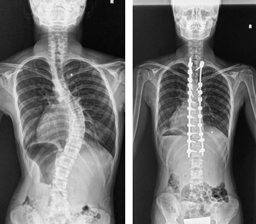

後方矯正固定術

せなかを切開してチタンなどで作られた椎弓根スクリューをせぼねに挿入して、ロッドと呼ばれる金属のバーで固定して、せぼねの矯正と固定を行います。術後に手術部の安静を保つために装具を3-6ヶ月程度着用します。

せなかを切開する場合が多いですが、状態によっては側方経路腰椎椎体間固定術(Lateral Lumbar Interbody Fusion: LLIF)や、経皮的椎弓根スクリュー(Percutaneous Pedicle Screw: PPS)をはじめとした体への負担を軽減する手法も取り入れられています。

手術時間は4時間程度で、入院期間はこどもの患者様で2週間程度、大人の患者様では2週間程度で場合によってはリハビリテーション病院へ転院をしていただき、さらにリハビリテーションを行います。